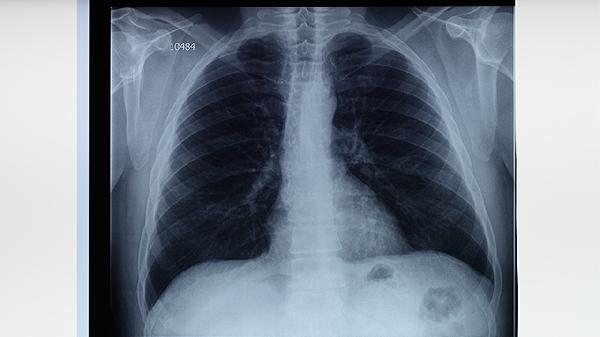

原發(fā)性肺結(jié)核多見于兒童和青少年,通常由初次感染結(jié)核分枝桿菌引起。病變多位于肺上葉下部或下葉上部靠近胸膜處,可伴隨肺門淋巴結(jié)腫大。部分患者可能出現(xiàn)低熱、盜汗、乏力等非特異性癥狀,胸部X線可見原發(fā)病灶與淋巴管炎、肺門淋巴結(jié)炎組成的啞鈴狀陰影。治療需規(guī)范使用異煙肼片、利福平膠囊、吡嗪酰胺片等抗結(jié)核藥物。

血行播散型肺結(jié)核包括急性粟粒型肺結(jié)核和亞急性/慢性血行播散型肺結(jié)核。急性粟粒型肺結(jié)核起病急驟,表現(xiàn)為高熱、寒戰(zhàn)、呼吸困難,胸部影像學(xué)可見雙肺均勻分布的粟粒樣結(jié)節(jié)。亞急性或慢性血行播散型肺結(jié)核癥狀相對較輕,可能出現(xiàn)咳嗽、消瘦等癥狀。該類型需聯(lián)合使用乙胺丁醇片、鏈霉素注射液等藥物進行強化治療。

繼發(fā)性肺結(jié)核是成人最常見的肺結(jié)核類型,多由體內(nèi)潛伏病灶復(fù)燃或再次感染所致。病變多位于肺尖或鎖骨下區(qū),可表現(xiàn)為浸潤性、空洞性、干酪樣肺炎等多種形態(tài)。典型癥狀包括咳嗽、咳痰、咯血、胸痛等,痰涂片檢查陽性率較高。治療需根據(jù)藥敏結(jié)果選擇敏感藥物,如利福噴丁膠囊、左氧氟沙星片等。